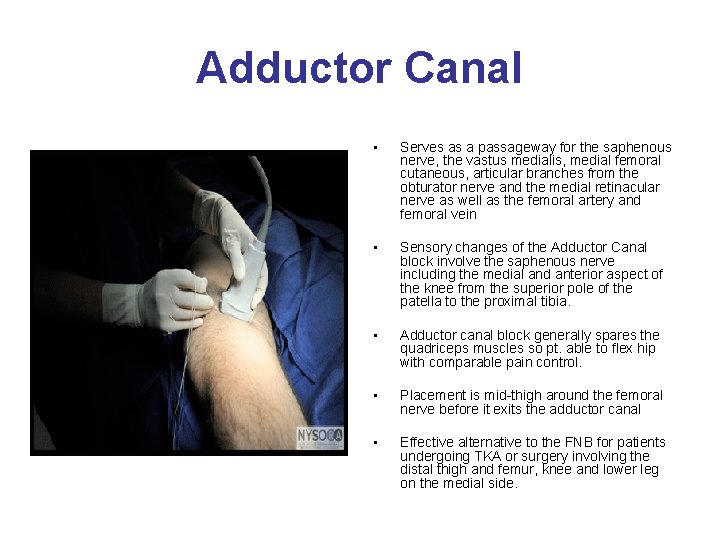

Adductor Canal • Serves as a passageway for the saphenous nerve, the vastus medialis, medial femoral cutaneous, articular branches from the obturator nerve and the medial retinacular nerve as well as the femoral artery and femoral vein • Sensory changes of the Adductor Canal block involve the saphenous nerve including the medial and anterior aspect of the knee from the superior pole of the patella to the proximal tibia. • Adductor canal block generally spares the quadriceps muscles so pt. able to flex hip with comparable pain control. • Placement is mid-thigh around the femoral nerve before it exits the adductor canal • Effective alternative to the FNB for patients undergoing TKA or surgery involving the distal thigh and femur, knee and lower leg on the medial side.